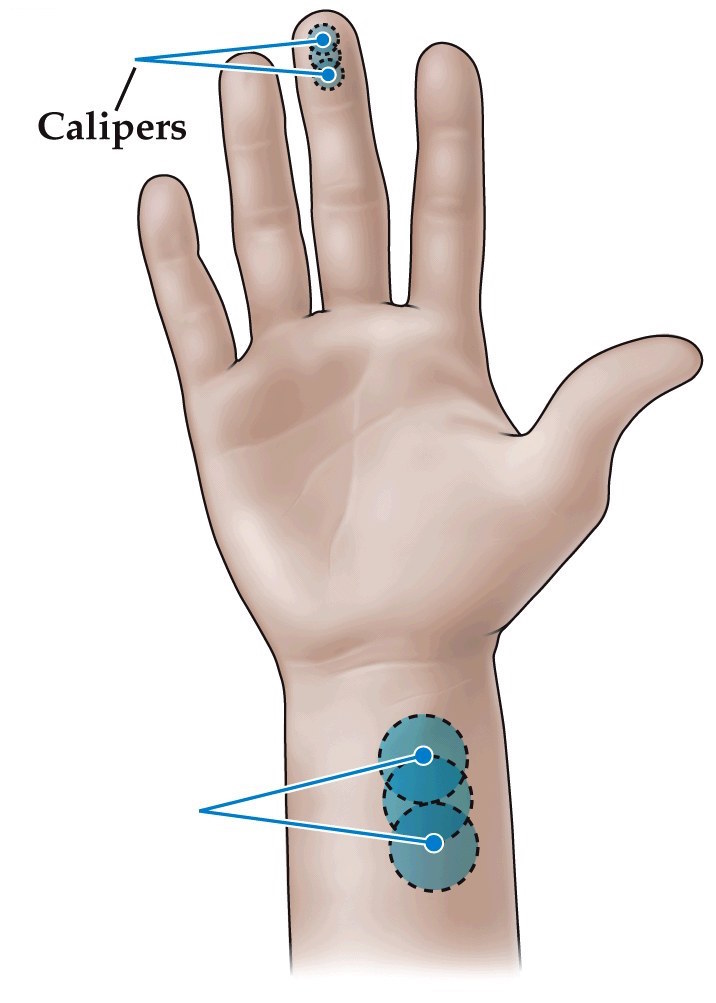

Differences in mechanosensory discrimination across the body surface

- The accuracy of our sense of touch is not the same all over the body

- Can use two-point discrimination tests to show this

- Fingers can distinguish things 2 mm apart, forearms 40 mm apart

- Mechanosensory receptors are more numerous in finger tips and have smaller receptive fields

- Doesn't explain everything about ability to discriminate two points. The CNS is also involved with discrimination. Two point thresholds vary with practice, and depend on the stimulus

Receptive field size across the body surface

- Receptive field (RF)– the area in the periphery within which sensory stimulus can modulate the firing of the sensory neuron

- Spatial resolution of the RF:

- Size– smaller RF, higher resolution

- Density– higher cell density, higher resolution

- Two-point discrimination test